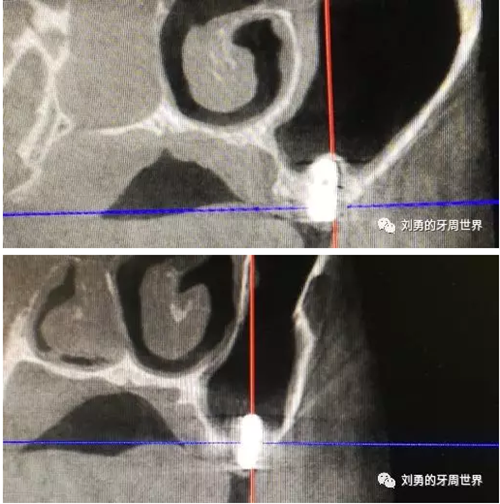

患者,男性,47歲,吸煙史30年,每天一包,8月前因左上56缺失,骨高度不足,在外院行上頜竇內(nèi)提升植骨手術(shù)。術(shù)前ct如下圖:

內(nèi)提升植骨后4個(gè)月,在外院行種植體植入,B5植入種植體3.5X10mm,B6植入種植體4.0X10mm,術(shù)后4個(gè)月后行二期手術(shù),術(shù)中B5種植體松動(dòng),未敢處理,B6放置愈合基臺(tái)。二期手術(shù)前復(fù)查ct如下圖(可見B56種植體竇內(nèi)成骨很少,種植體距離過近):